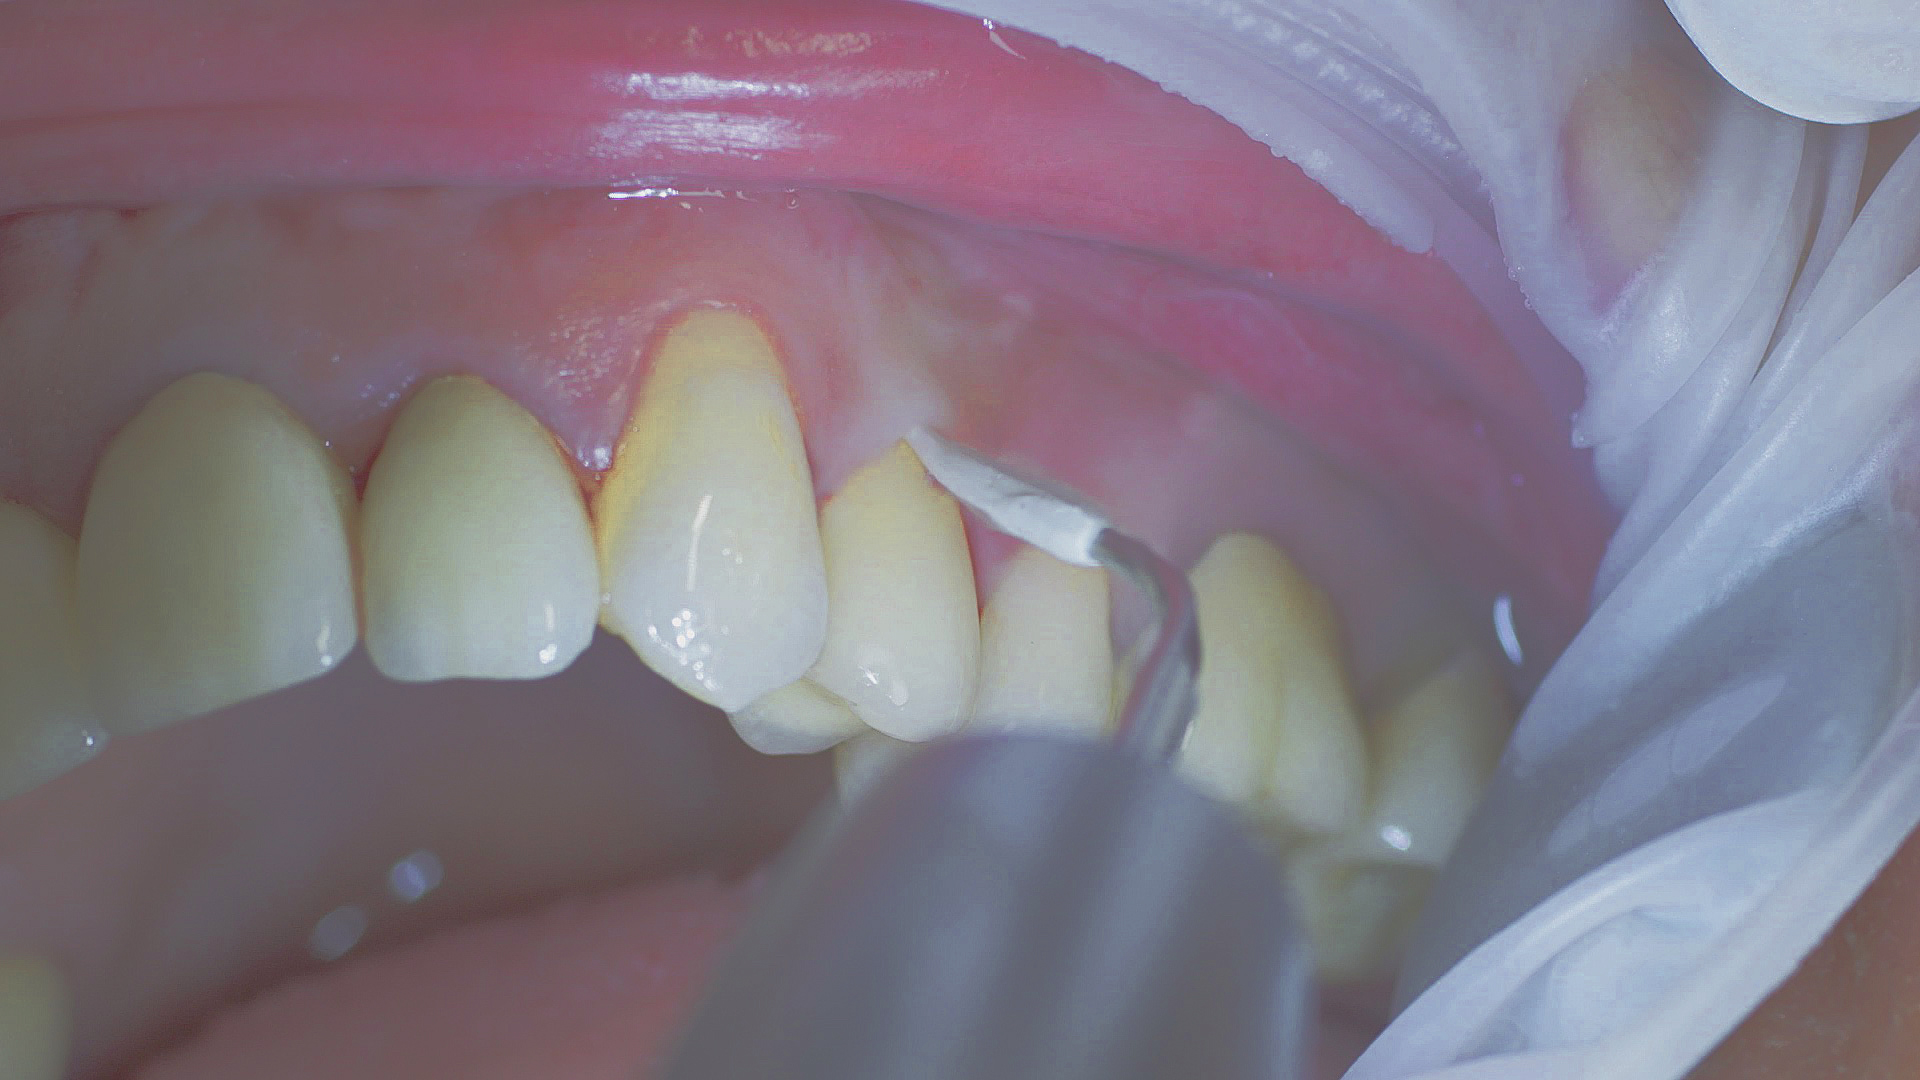

Removal of subgingival coatings (debridement) is carried out using sonic or ultrasonic devices and special periodontal tips as initial periodontal treatment (Fig. 3). Manual instruments can also be used. Further surgical and/or regenerative measures may be necessary, depending on the situation.

Sonar technology, W&H Proxeo with 1AP tip

Fig. 3: If marginal periodontitis is diagnosed, the initial debridement can be carried out very efficiently with an air scaler (sonar technology, W&H Proxeo with 1AP tip)